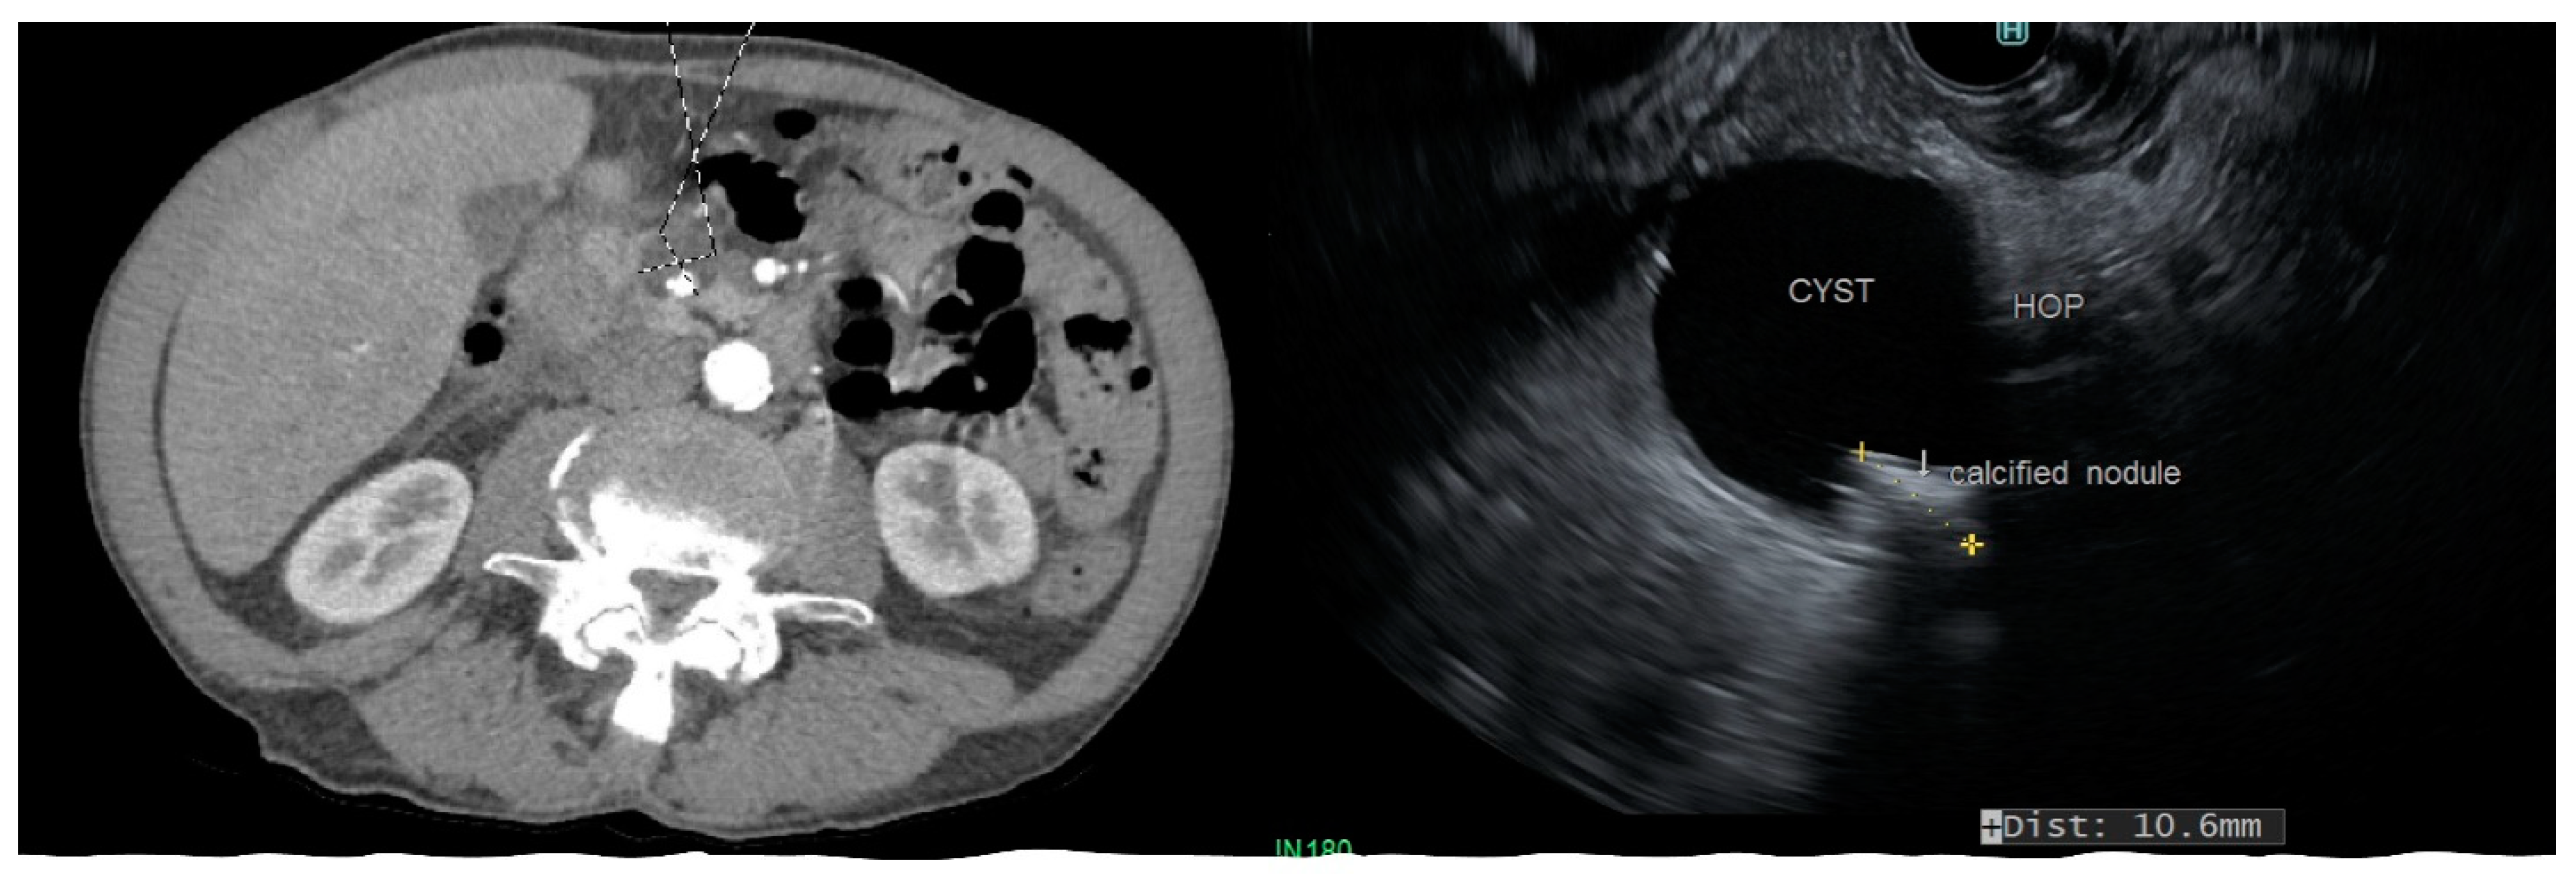

Figure 2.

CT scan and endoscopic ultrasound demonstrating a side-branch IPMN involving the head of pancreas (HOP) with a calcified mural nodule.

IPMN: The distribution of cysts in relation to the main pancreatic duct determines the malignant behavior of IPMN. Consequently, IPMN are classified as the main-duct IPMN (MD-IPMN) when MPD is dilated due to the direct involvement for more than 5 mm without a visible cyst, branch-duct IPMN (BD-IPMN), when there is a cyst, >5 mm without dilated MPD, and mixed-type when there is one or more PC > 5 mm along with the involvement of MPD. MD-IPMN and mixed-type IPMN have a higher risk of harboring invasive adenocarcinoma (approximately 45%) and high-grade dysplasia (approximately 60%), while BD-IPMN are at lower risk (16–20%) [11]. Moreover, the rate of cyst growth on follow-up can predict the risk of malignant behavior in BD-IPMN [12]. MPD dilation >10 mm in MD-IPMN, with a cyst diameter >40 mm in BD-IPMN, and the presence of a large mural nodule on EUS favor malignancy (Figure 2) [13]. Pergolini et al. followed up patients with BD-IPMN for over 10 years and found that the risk of malignancy was significant (approximately 8%) for cysts > 1.5 cm even after the five years of suggested surveillance period [14].

CT and MRI have a comparable sensitivity at differentiating malignant from benign PC, and both have equivalent accuracy at making a specific diagnosis (50–60%); however, the rate of misdiagnosis is remarkable with either imaging modality (>50%) [25,26,27]. MRI is considered better than CT at evaluating cyst morphology. Consequently, the major advantages of MRI and MRCP over CT scans are characterizing the aggressiveness of small cysts and detecting high-risk morphologic features, such as the mural nodule, septal thickening, and cyst communication with MPD (Figure 2).